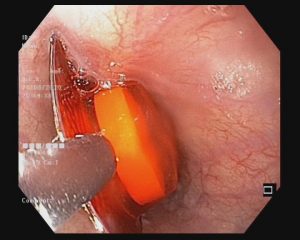

Rắn lục đuôi đỏ thuộc nhóm rắn lục, nọc độc rắn lục đuôi đỏ có thể gây tổn thương hoặc hoại tử cơ, suy thận, rối loạn đông máu – tức là làm cho nạn nhân dễ bị chảy máu hơn và khó đông hơn.